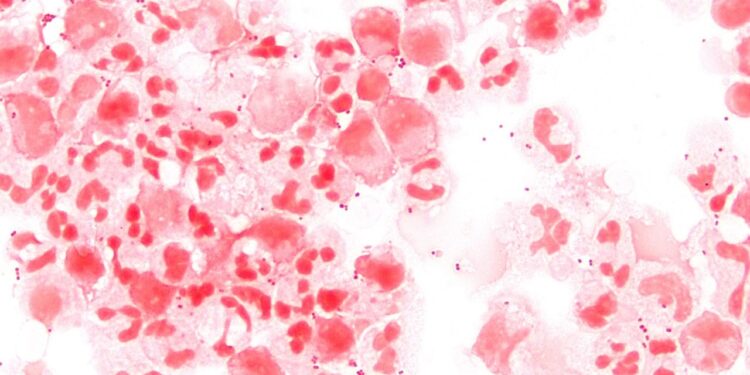

1 de 1 Neisseria meningitidis, a bactéria que causa a meningite meningocócica. — Foto: Wikimedia/Divulgação

Neisseria meningitidis, a bactéria que causa a meningite meningocócica.

Wikimedia/Divulgação